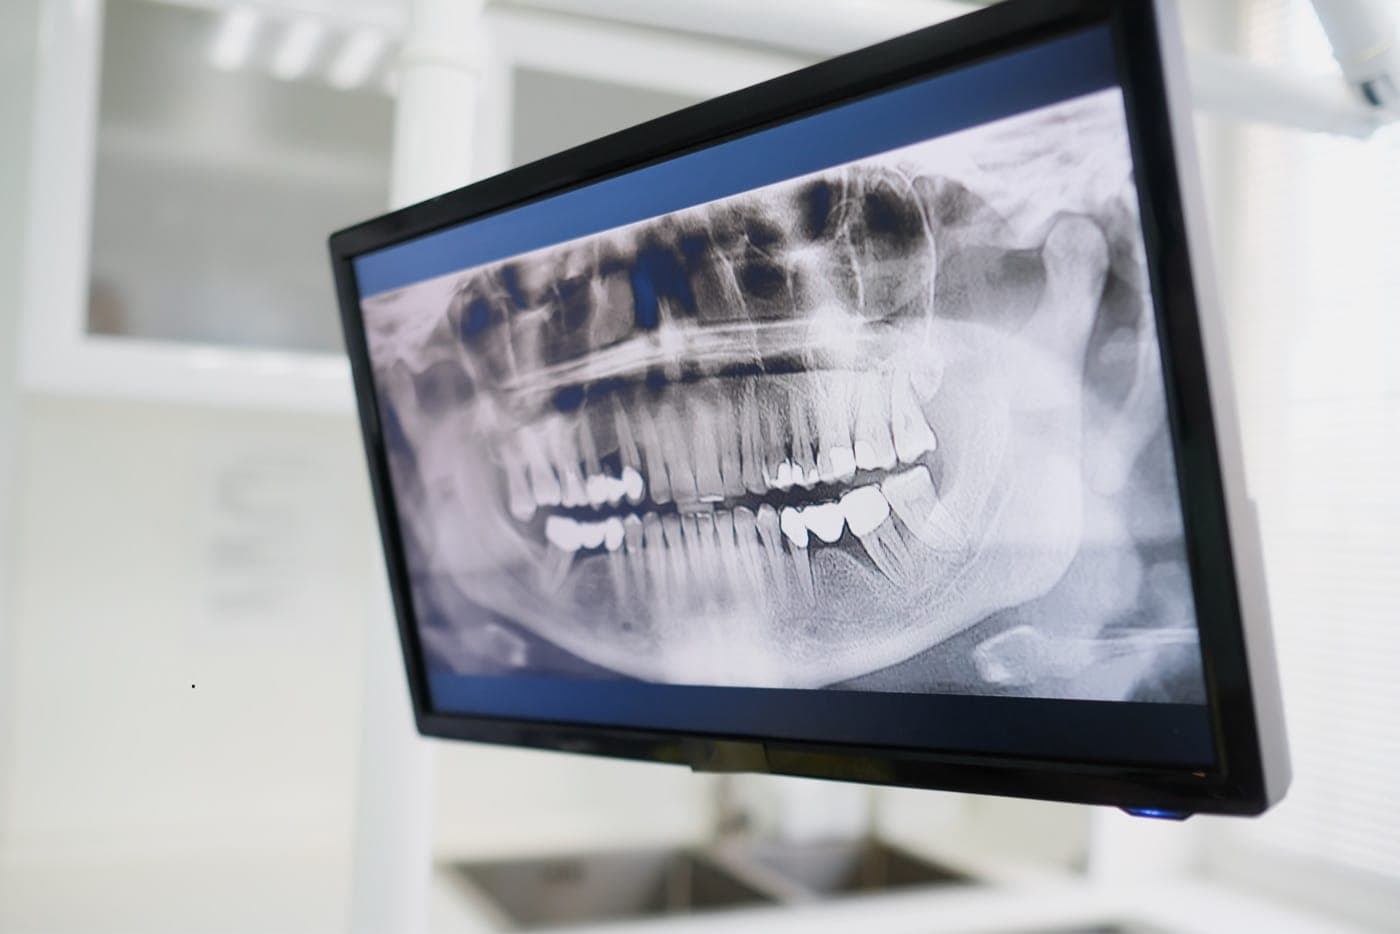

Panoramic X-Ray

A two-dimensional imaging method that allows all teeth, jawbones, and adjacent structures to be assessed in a single image.